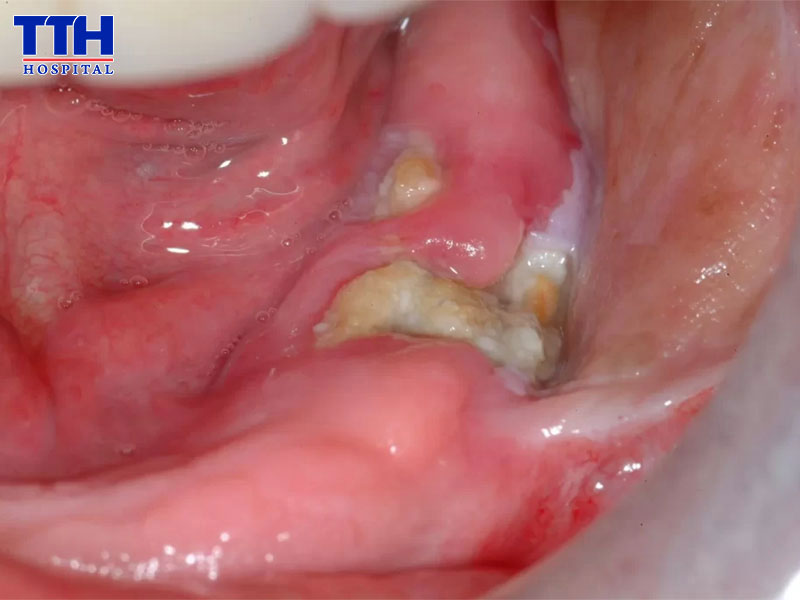

So với các răng khác, răng khôn (răng số 8) thường tiềm ẩn nhiều nguy cơ hơn khi nhổ. Nguyên nhân là bởi răng khôn mọc ở vị trí sâu nhất trên cung hàm nên rất khó vệ sinh. Ngoài ra, nhiều trường hợp răng khôn mọc lệch, mọc ngầm hoặc bị lợi trùm, khiến vi khuẩn dễ tích tụ và gây viêm nhiễm.

Trong quá trình nhổ răng khôn, bác sĩ có thể phải thực hiện tiểu phẫu như:

• Rạch nướu

• Tách mô lợi

• Chia nhỏ thân răng để lấy ra ngoài

Chính vì vậy, vùng mô xung quanh răng khôn thường chịu nhiều tác động hơn so với nhổ răng thông thường. Nếu quy trình thực hiện không đảm bảo hoặc chăm sóc hậu phẫu không đúng cách, nguy cơ viêm nhiễm sau nhổ răng khôn sẽ cao hơn đáng kể.